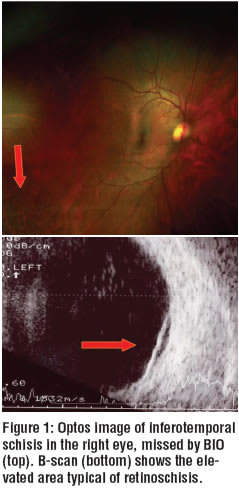

You can see the clinical benefit of this particular device in a 54 year-old female who was referred for evaluation of a superotemporal retinoschisis in her left eye. Her primary optometrist discovered this during a dilated fundus examination of both eyes with BIO.

Imaging with the Panoramic 200 revealed a larger, but flatter inferotemporal retinoschisis in the patient’s right eye. This was missed by BIO on previous examinations (see figure 1).